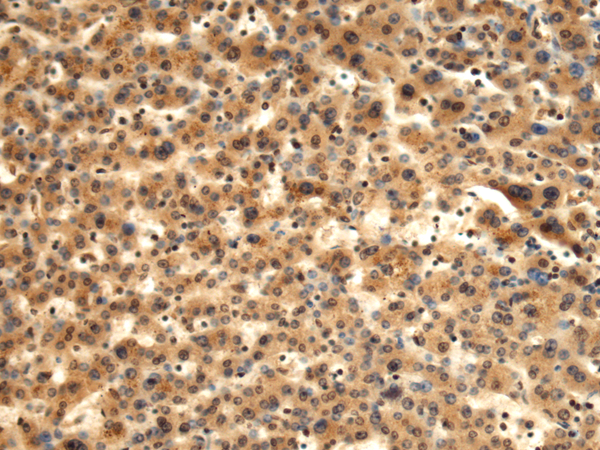

分类: 科研抗体货号: P10440别名: STK32; STKG6; YANK2; HSA250839应用: WB,IHC反应种属: Human, Mouse